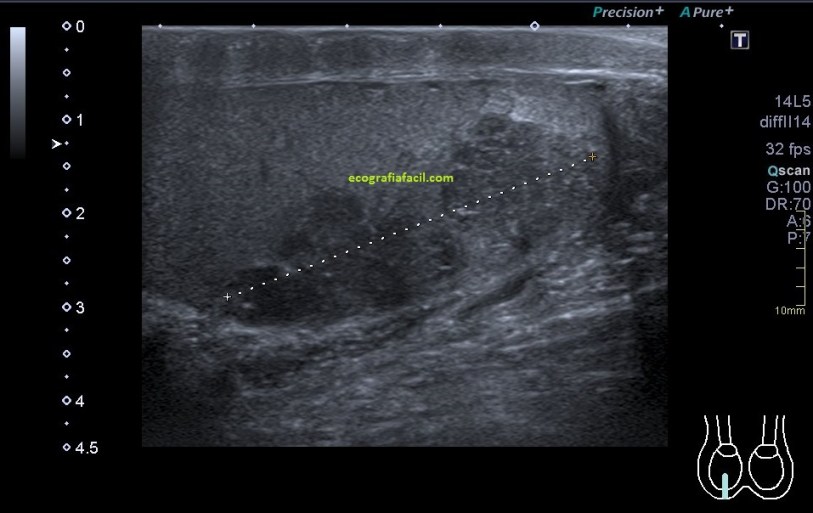

Compara la imagen 1 y la 2, grábala en tu memoria fotográfica. Ambas son unas imágenes en corte longitudinal del teste derecho de dos pacientes distintos.

Una vez que hemos encontrado la lesión, es momento de estudiarla detenidamente, su aspecto, tamaño bordes y vascularización son vitales para que la radióloga pueda efectuar un informe.

La imagen 3 y 4 son parte estudian en eje largo y corto las medidas de la lesión en los tres ejes del espacio, en ocasiones, podemos tener más de una lesión. Siempre super atentos si las lesiones son intra o extratesticulares.

El aspecto de esta lesión, su semiología ya la has visto en estos dos casos diferentes, pero tienen en común, de modo general, hipoecogenicidad, heterogenicidad, bordes irregulares, con aspecto polilobulado y de tamaño y número variable.